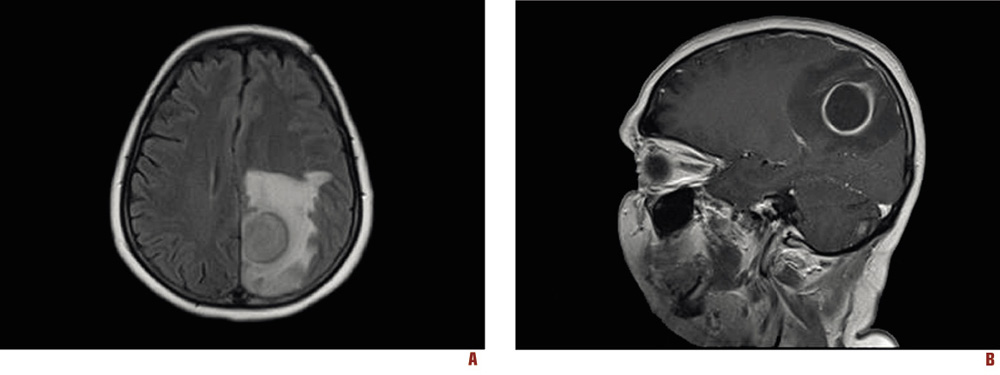

A brain computerized tomography (CT) scan revealed an intracranial mass in the left hemisphere with surrounding edema resembling an abscess. An additional brain magnetic resonance imaging (MRI) study was performed, which corroborated the diagnosis depicting a 3×2.7 cm brain abscess (Figure 1).

Figure 1. Brain MRI at admission. Axial view (A), sagittal view (B)